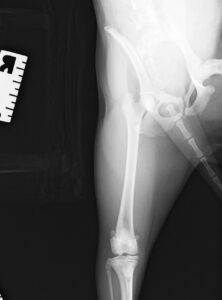

9ヶ月の柴犬の女の子が、高所から落下してしまい左後肢を痛めたとのことで来院されました。左後肢は足を着くことができず、レントゲン検査の結果、大腿骨(太ももの骨)の複雑骨折を認めました。

大腿骨の膝に近い部分が骨折してしまっており、さらに単純な骨折ではなかったため、内側と外側にそれぞれプレートを設置し固定しました。

関節に近い場所の手術であったためどうしても術後は関節がある程度拘縮(曲げ伸ばししづらくなる)してしまいますが、徐々に足を着けるようになってくれ、リハビリの効果もあり今では元通り運動できるように回復してくれました。

大腿骨遠位の骨折は特に若齢の犬猫においてしばしば発生します。若齢時には多くの骨の両端に成長板という骨を作る場所があり、その場所は強い力がかかった際に骨折しやすいためです。単純な骨折の場合にはピンだけで整復が可能なことも多くありますが、今回のような状況ではプレート固定も適応になります。どちらにしても手術後に関節の拘縮が起きやすく、術後のリハビリも重要になってきます。当院ではリハビリに特化したスタッフも在籍し、術後のケアもご家族と共に実施していきますので安心して手術を受けて頂くことができます。